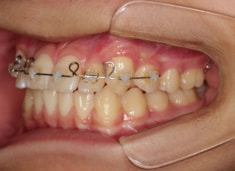

治療開始時

FX(フェイシャルアキシス)は85度なので東洋人の平均値に近く、下顎が前方に過剰成長するリスクは強くはありません。

しかしやはり上顎は劣成長で、下顎が優位な状態ではあります。

上下顎のギャップはありますが、顔面自体の幅径は良好な値を示していますので、スペース不足は拡大することによって解決できポテンシャルはあると考えられます。

左右の非対称もさほど強くありません。